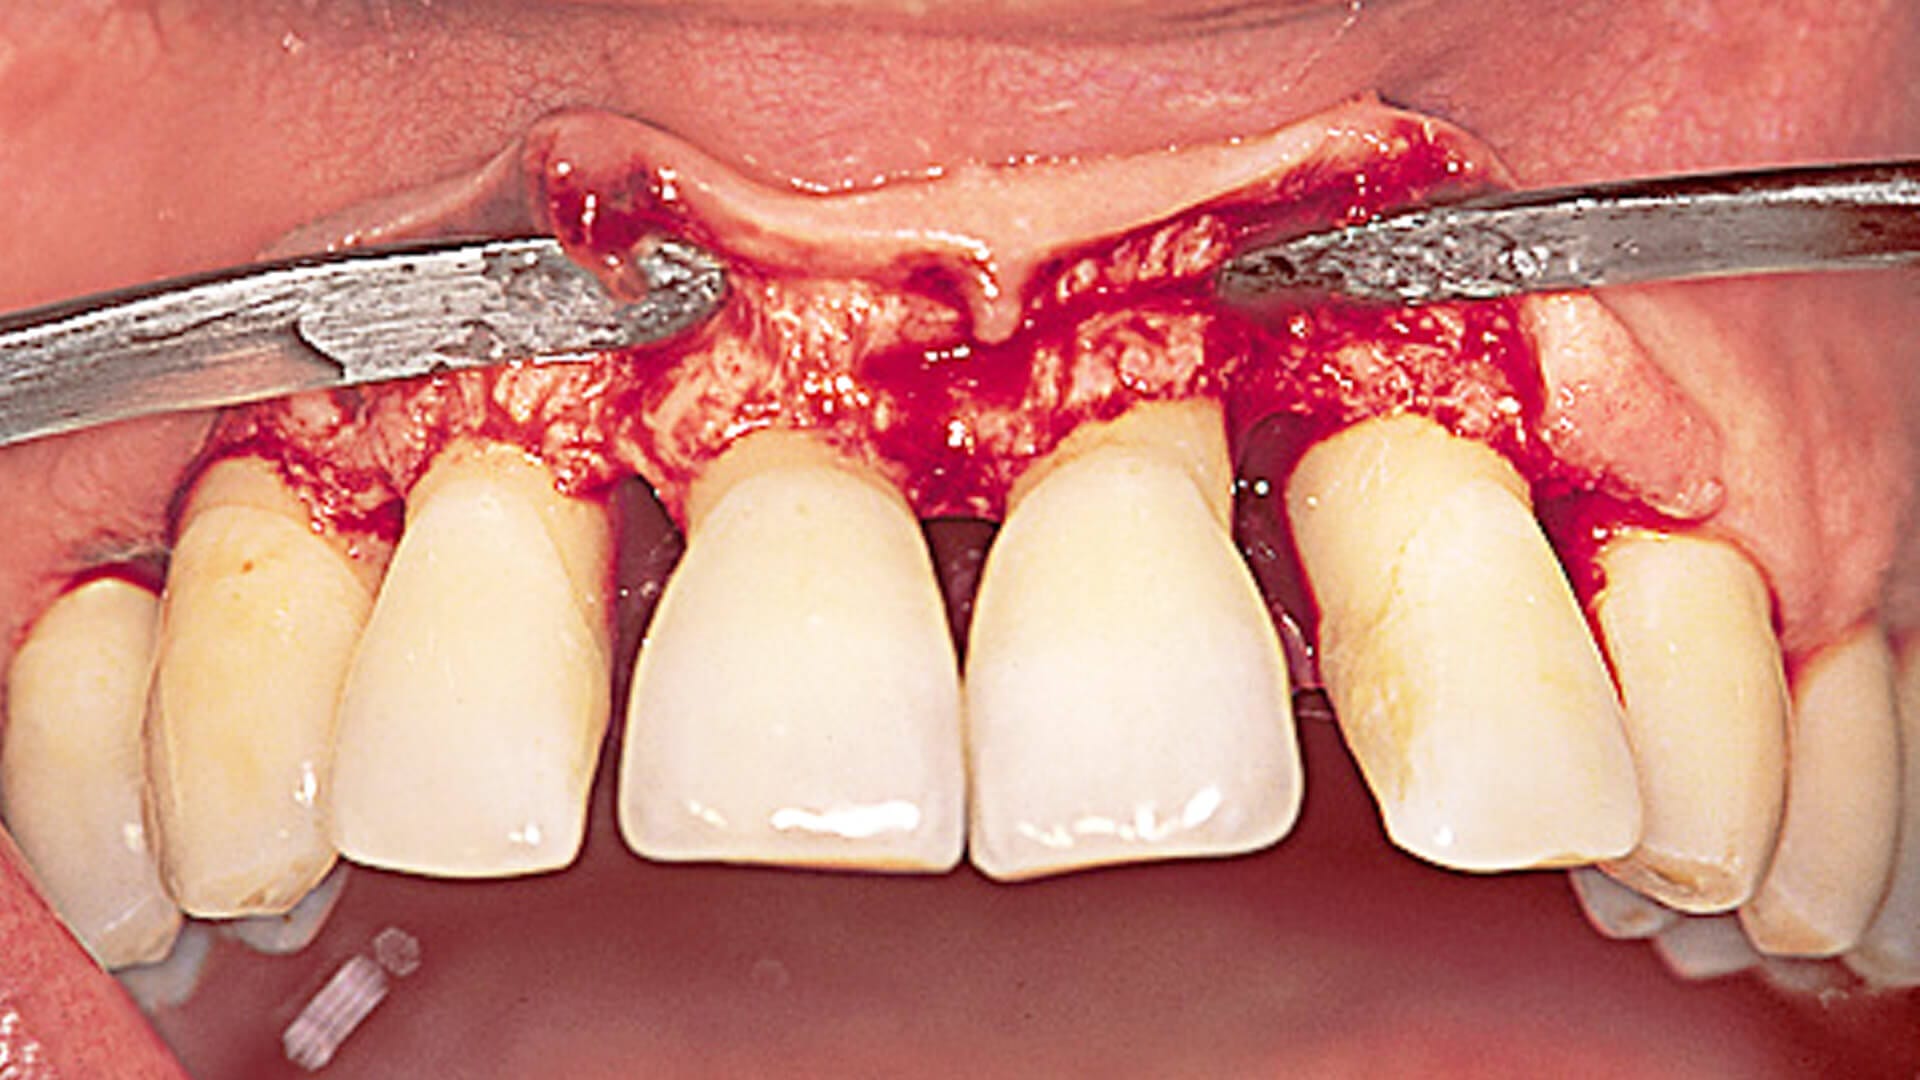

Gingival flap surgery requires your dentist to cut a small flap so that they can lift the gum and access any pockets that need cleaning and closing. Tarter will be removed, and if needed, the bone may be slightly reshaped too. Then the flap of gum is stitched back in place and left to heal.

This procedure reverses those pockets caused by inflammation, and gives your gums a better chance to heal from gingivitis.